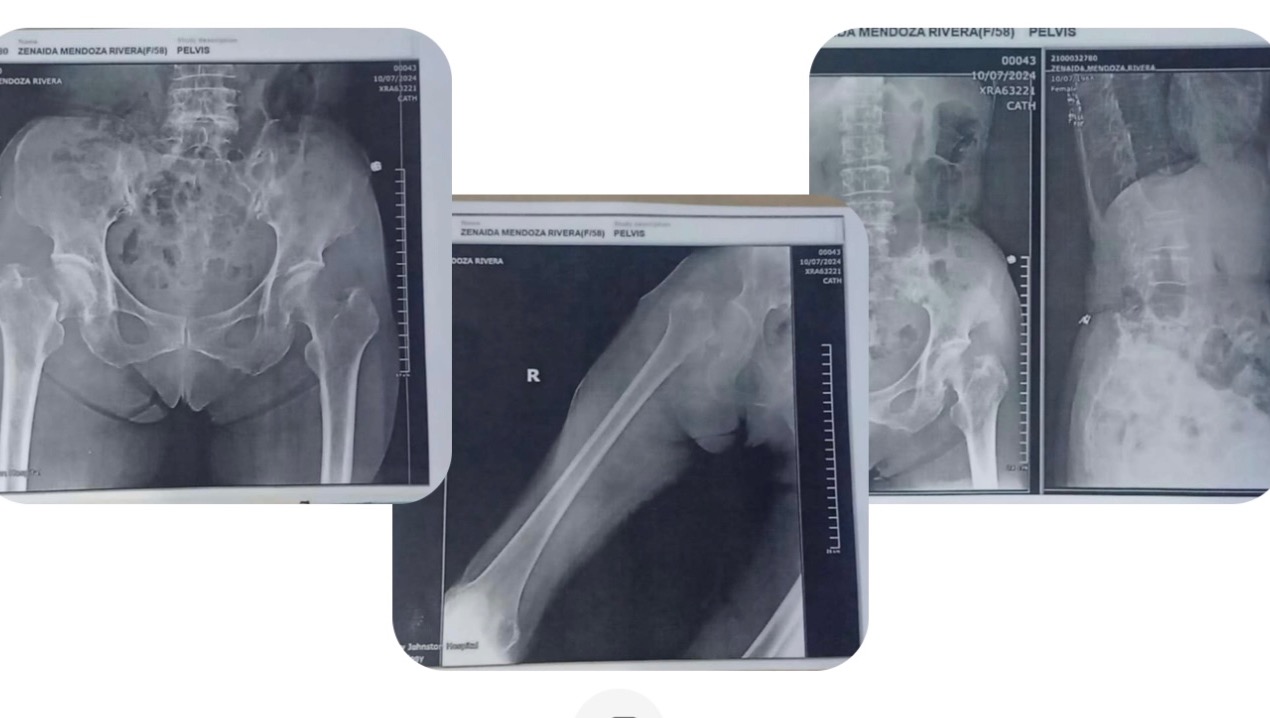

I just want to thank you from the bottom of my heart for reading and extending any help or prayer for my mother. Her name is Zenaida Rivera 76 y/o and a retired grade school teacher. My mother accidentally took a hard fall and sustained a fractured femur on her right hip socket and will need to undergo a hip surgery in the Philippines. It’s been very difficult for me and my family dealing with this ordeal. Being so far away from them makes it even more challenging . There’s no such thing as Medicare, Medi-cal back home and hospitalization cost is out of pocket and you have to buy every piece of supply not provided by hospitals. I wish I can shoulder all the cost and maintenance for my mother that will probably reach up to $5k plus. I’m also providing for my father’s care who’s partially paralyzed because of a stroke. At this time of health adversity, I know that asking for help is just being human and there’s nothing to be ashamed of. Me and my family are so grateful my for your support and compassion I understand that all of us have our own problems to deal with and I apologize to be an added burden to your lives. She’s scheduled to be for surgery today. It was supposed to be about a week ago but we had to go by the surgeon’s availability . My mother has been so brave and endured so much in her life. I admire her strength and courage! How I wish I can take her pain away but I know God is watching over her. Thank you so so much for anything that you can manage. I will never forget you!!! This is not circulated online or any social media. It was only sent to family and friends for I don’t want to be perceived as begging for attention and taking advantage of people. God bless all of you!!! Take care!